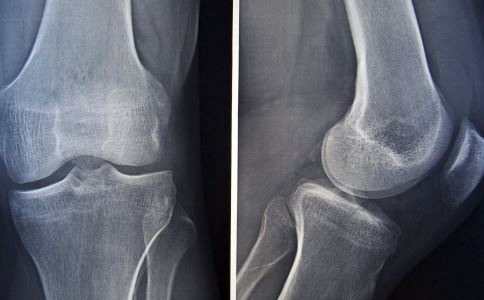

骨折后多数患者会感到疼痛难忍,需要使用止疼药物。